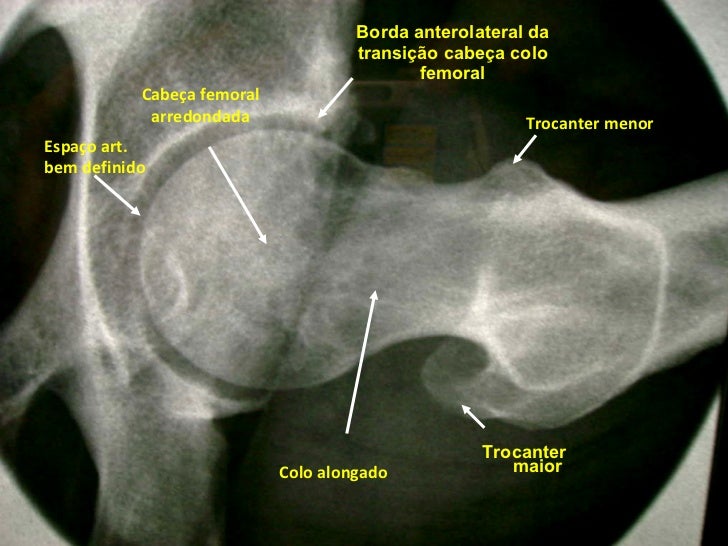

Borda anterolateral da transição cabeça colo femoral <ul><li>Trocanter maior </li></ul>Trocanter menor Cabeça femoral arre...

<ul><li>Esta radiografia mostra bem uma boa mobilidade na incidência de Ducroquet. Podemos visualizar o colo femoral bem  ...

29. 30. Borda anterolateral da transição cabeça colo femoral <ul><li>Trocanter maior </li></ul>Trocanter menor Cabeça femoral arredondada Colo alongado Espaço art. bem definido

37. 38. <ul><li>Esta radiografia mostra bem uma boa mobilidade na incidência de Ducroquet. Podemos visualizar o colo femoral bem alongado, trocanter menor visível em perfil internamente. </li></ul>